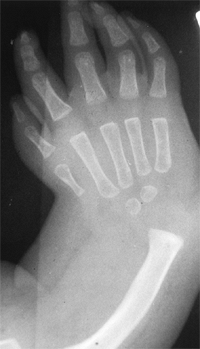

![]() |

Figure 23.2 Clinical photographs of hemiplegic tendon transfers for improving hand and upper limb function. A: Preoperative view of dynamic elbow flexion, forearm pronation, wrist flexion, and ulnar deviation with poor assist function. B: Postoperative active elbow extension with maintenance of active elbow flexion. C: Postoperative active wrist extension with the thumb out of the palm for active pinch. D: Postoperative active grasp function with the thumb abducted and extended actively. (Courtesy of Ann Van Heest, MD)